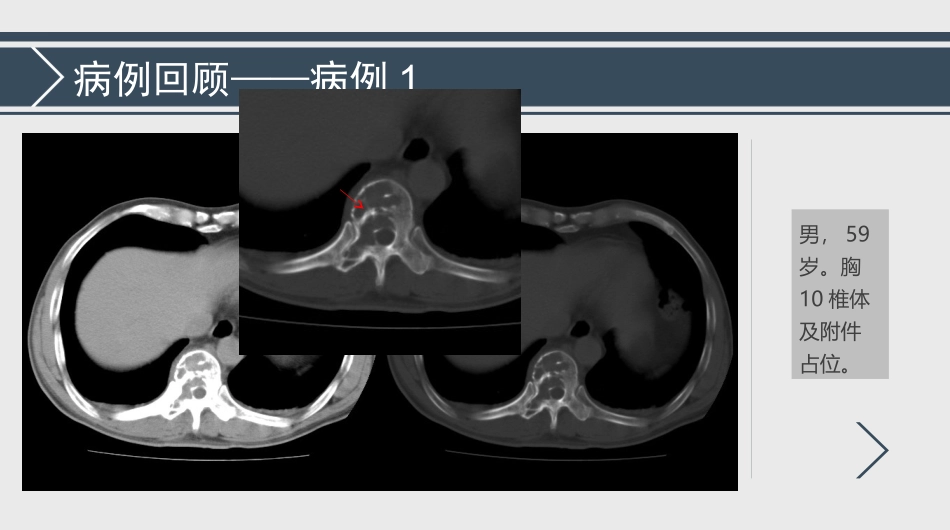

阅片蒋诚诚2019.01.23病例回顾——病例1男,59岁。胸10椎体及附件占位。胸10椎体溶骨性骨质破坏,边缘硬化,病灶内见残存骨嵴MR增强扫描示病灶累及胸10椎体及右侧椎弓根、横突,明显强化,病灶内残存骨嵴T1WI呈低信号。结果?检查所见:术中送灰白组织1.5*1.0*1.3cm,质软,鱼肉样,无包膜。术后又送灰红碎组织一堆5.0*4.5*0.5cm,质软,鱼肉样。印象:(胸10椎体及附件)浆细胞骨髓瘤。建议:MUM-1、CD38、CD138、Lambda(弥漫+),Kappa(少数、灶性弱+),CD3、CD20(-),Ki-67(15-20%+)。病例回顾——病例2女,51岁,右肩疼痛1月余。右肱骨近端占位。右肱骨近端髓腔内软组织肿块,边界清,临近骨皮质呈“虫蚀状”破坏。右肱骨近端稍短T1(与肌肉对比)长T2信号影,边界清晰,累及周围骨皮质及软组织,未见瘤周骨髓水肿。结果?检查所见:术中见髓腔内鱼肉样改变、质软异常组织、肱骨骨皮质菲薄(鸡蛋壳样改变)。术中送(右肱骨)灰白红组织一块1.5*1.5*0.6cm,切面灰红、灰白,实性,质软。术后(右肱骨)送灰红碎组织一堆6.0*6.0*1.0cm,含部分骨组织。印象:(右肩)髓内浆细胞瘤。建议:B:CD56(-),CD138(+),CD38(-)、Lambda(-),Kappa(+),Ki-67:(+)约10%。骨孤立性浆细胞瘤Solitaryplasmacytomaofbone,SPB淋巴细胞的分化及成熟正常情况下,人体不同来源的浆细胞分泌不同化学结构和免疫特性的免疫球蛋白;正常情况下,人体不同来源的浆细胞分泌不同化学结构和免疫特性的免疫球蛋白;异常情况下,相同来源的浆细胞恶变增生,分泌大量同源的、结构完全均一的单克隆免疫球蛋白。异常情况下,相同来源的浆细胞恶变增生,分泌大量同源的、结构完全均一的单克隆免疫球蛋白。前B细胞前B细胞前B细胞前B细胞浆细胞病浆细胞瘤浆细胞瘤浆细胞瘤是以浆细胞异常增生为特征的恶性肿瘤WHO分类:浆细胞性骨髓瘤(多发性骨髓瘤,mutiplemyeloma,MM)孤立性浆细胞瘤(solitaryplasmacytoma,SP)•髓外浆细胞瘤(extramedullaryplasmacytoma,EMP)•骨孤立性浆细胞瘤(solitaryplasmacytomaofbone,SPB)浆细胞白血病(PCL)多发性骨髓瘤(MM)骨孤立性浆细胞瘤(SPB)髓外浆细胞瘤(EMP)骨骼受侵全身多发骨质破坏除原发病灶外,其他骨骼及骨髓均正常正常软组织肿块发生率15%,头、胸骨、锁骨多见,胸壁、锥体旁也可见常见常见于鼻咽部和鼻窦血象贫血正常正常M蛋白异常99%伴有血/尿M蛋白异常10-20%伴有血/尿M蛋白异常15%-20%伴有血/尿M蛋白异常骨髓象异常,浆细胞>15%正常正常感染常见少见少见肾损常见少见少见SPB——临床特点流行病学:发病率约占浆细胞瘤的5%发病年龄约40-60岁,中位年龄约50岁较多发性骨髓瘤早10年男女发病率约2:1SPB——诊断标准由单克隆性浆细胞引起的单独骨的破坏,经病理证实为浆细胞瘤无多发病灶,无远处骨受累,可伴有病灶区邻近骨受侵骨髓象阴性,浆细胞比例<5%-10%免疫球蛋白水平大致正常,无或仅表现为低水平的血清及尿单克隆蛋白无高钙血症、浆细胞瘤导致的肾功能不全、贫血或骨质损害等终末器官受损SPB——临床特点临床表现:发病部位:脊柱60%,周围及四肢骨骼25%-30%,好发部位依次为骨盆、股骨、肱骨和肋骨,颅骨受侵罕见局部疼痛/肿块或压痛,骨质破坏/病理性骨折累及脊柱,25%造成神经损伤(脊髓或神经根)无全身性疼痛、贫血、慢性肾功能衰竭、发热等全身症状SPB影像学表现——脊柱•胸椎最常累及;•单发椎体溶骨性骨质破坏,部分椎体压缩;•伴或不伴椎弓根及附件受累;•MRI信号不一:T1WI信号呈低及等低信号为主,T2WI呈高或混杂高信号;•软组织肿块形成,增强后明显强化;脊柱SPB•病变周围无瘤周骨髓水肿•椎间盘无受累,信号未见异常,椎间隙无狭窄•肿块可围绕或半围绕椎管生长,呈“围管征”或“袖套征”•增强瘤体及脊膜均明显强化,可显示类似脊膜尾征脊柱SPB•典型征象—微型脑征(轴位图像上,残存的骨嵴向破坏区生长,犹如深入脑回的脑沟)SPB影像学表现——四肢骨X线及CT表现:•轻度膨胀性、溶骨性、虫蚀状骨质破坏;•边界清晰,骨皮质变薄或中断(“破而不烂”),病变骨组织被软组织替...